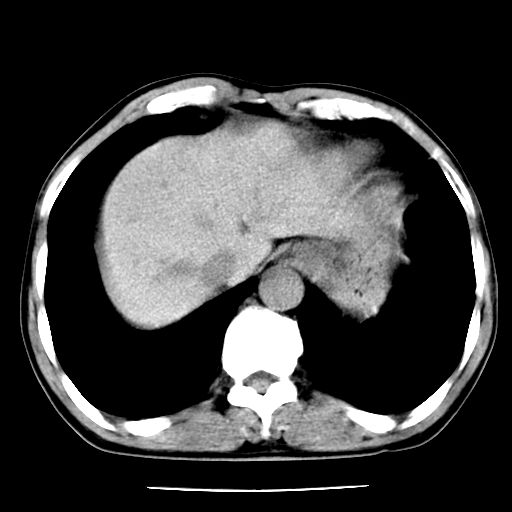

男,59岁,“结核性胸膜炎”30余年,胸部经常疼痛,多次x检查提示“肺部”炎症。腹部疼痛5日,b超提示:“肝内短管结石,余显示不清,建议进一步检查。”

两肺结核并右侧胸腔积液;脾脏、腹腔及腹膜后淋巴结结核[陈旧性];肝内胆管结石

胸部腹部都是结核(双肺。纵隔淋巴结,肝脏,脾脏,肠系膜)

两肺结核并右侧胸腔积液;脾脏、腹腔及腹膜后淋巴结结核[陈旧性];肝内胆管结石。直肠息肉?